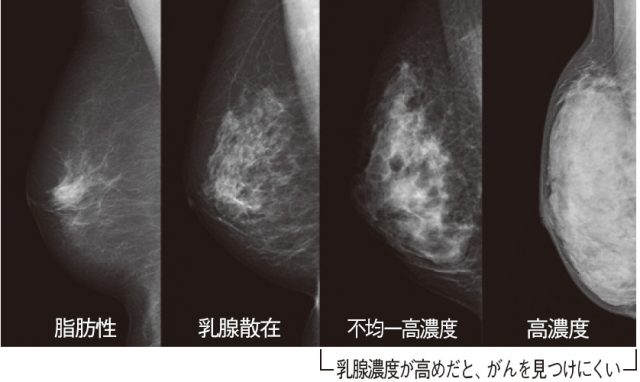

マンモグラフィの画像

マンモグラフィの画像をみると違いは明らかです。

右側の2つが高濃度乳房です。

【http://wol.nikkeibp.co.jp/article/column/20141215/196941/より引用】

高濃度乳房は、上述のとおり乳腺実質の割合が多いため、

マンモグラフィに癌がうつりにくく見逃しのリスクが伴います。

高濃度乳房では背景にある乳腺がマンモグラフィで白く描出されるため、同じように白く描出される乳がんが隠れてしまいやすいのです。